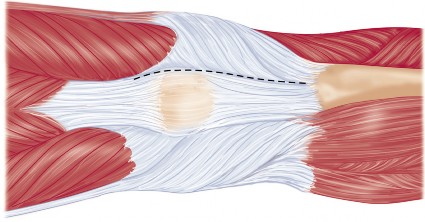

يركز هذا النهج على استخدام فتحة المفصل شبه الرضفية الإنسية المحدودة (Limited Medial Parapatellar Arthrotomy) وشق العضلة الرباعية المحدود، وهو جزء من مجموعة من الأساليب المعدلة التي توفر وصولاً ورؤية محدودين، ولكن يمكن تحويلها إلى نهج تقليدي إذا لزم الأمر. هذا يعني أن الجراح يمكنه البدء بتقنية أقل توغلاً، مع الاحتفاظ بالقدرة على التكيف إذا كانت الحالة تتطلب رؤية أوسع.

يُعد النهج شبه الرضفي الإنسي المحدود في جراحة استبدال مفصل الركبة الكلي بالحد الأدنى من التدخل الجراحي خيارًا مألوفًا ومتعدد الاستخدامات، وقد تطور مع إضافة أدوات أصغر وأكثر كفاءة. يتميز هذا النهج بقدرته على التكيف مع مجال العمليات المحدود في الركبة، مما يسمح بتشريح جراحي محدود دون المساس بالإجراء أو النتائج.

كيف يؤثر التدخل الجراحي المحدود على الأنسجة

في جراحة استبدال مفصل الركبة التقليدية، يتم إجراء شق كبير لتمكين الجراح من الوصول الكامل إلى المفصل ورؤية جميع الهياكل. هذا قد يتطلب قطعًا أوسع في العضلات والأوتار والأنسجة الرخوة المحيطة. في المقابل، يهدف النهج شبه الرضفي الإنسي المحدود إلى:

الحفاظ على العضلة الرباعية:

وهي العضلة الرئيسية المسؤولة عن تمديد الركبة. يقلل هذا النهج من قطع هذه العضلة أو فصلها، مما يؤدي إلى تعافٍ أسرع لقوتها ووظيفتها.

تقليل تضرر الأنسجة الرخوة:

عن طريق العمل من خلال "نافذة" جراحية أصغر، يتم تقليل التلاعب بالأنسجة والأربطة المحيطة، مما يقلل من النزيف والتورم والألم بعد الجراحة.

هذا الحفاظ على الأنسجة هو المفتاح وراء الفوائد التي يقدمها استبدال مفصل الركبة بالحد الأدنى من التدخل الجراحي، ويحرص الأستاذ الدكتور محمد هطيف على تطبيق هذه المبادئ بدقة لتعظيم فوائدها لمرضاه.